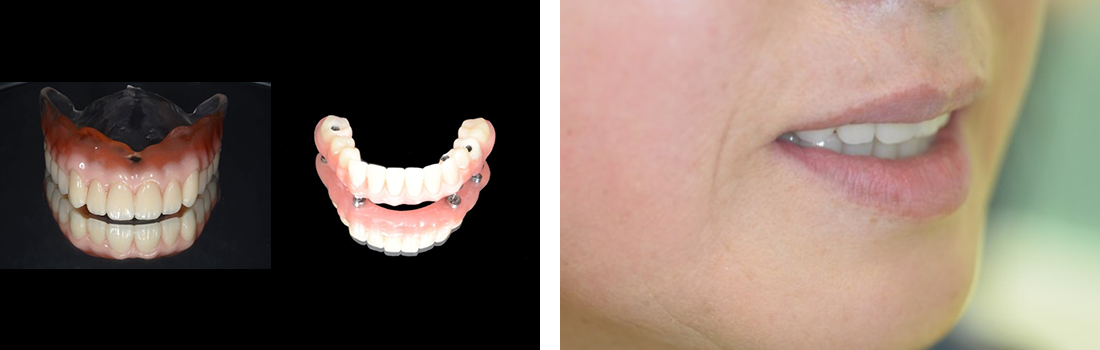

All-on-4症例 Case1

Treatment cases

Before

After

インプラント治療は、咀嚼機能の改善だけでなく、 口腔周囲筋の発達により見た目の若返りにも貢献してくれます。